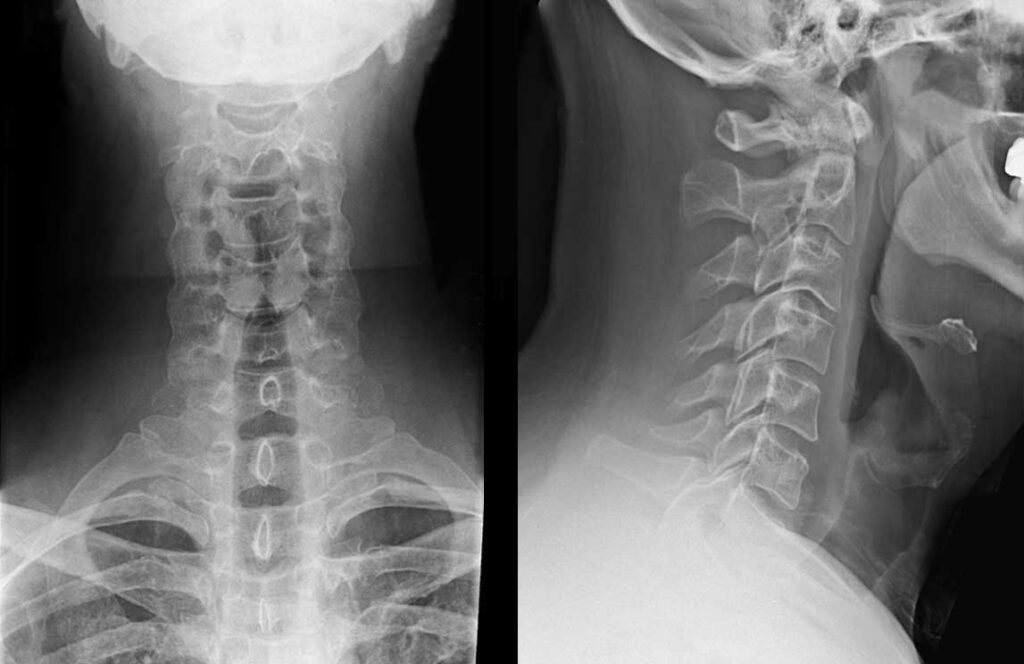

Nếu nghi ngờ bệnh ở giai đoạn nặng hơn hoặc muốn xác định rõ nguyên nhân bệnh, bác sĩ có thể yêu cầu:

- Chụp X-quang, CT hoặc MRI: Chẩn đoán thông qua hình ảnh tình trạng đĩa đệm của bệnh nhân.